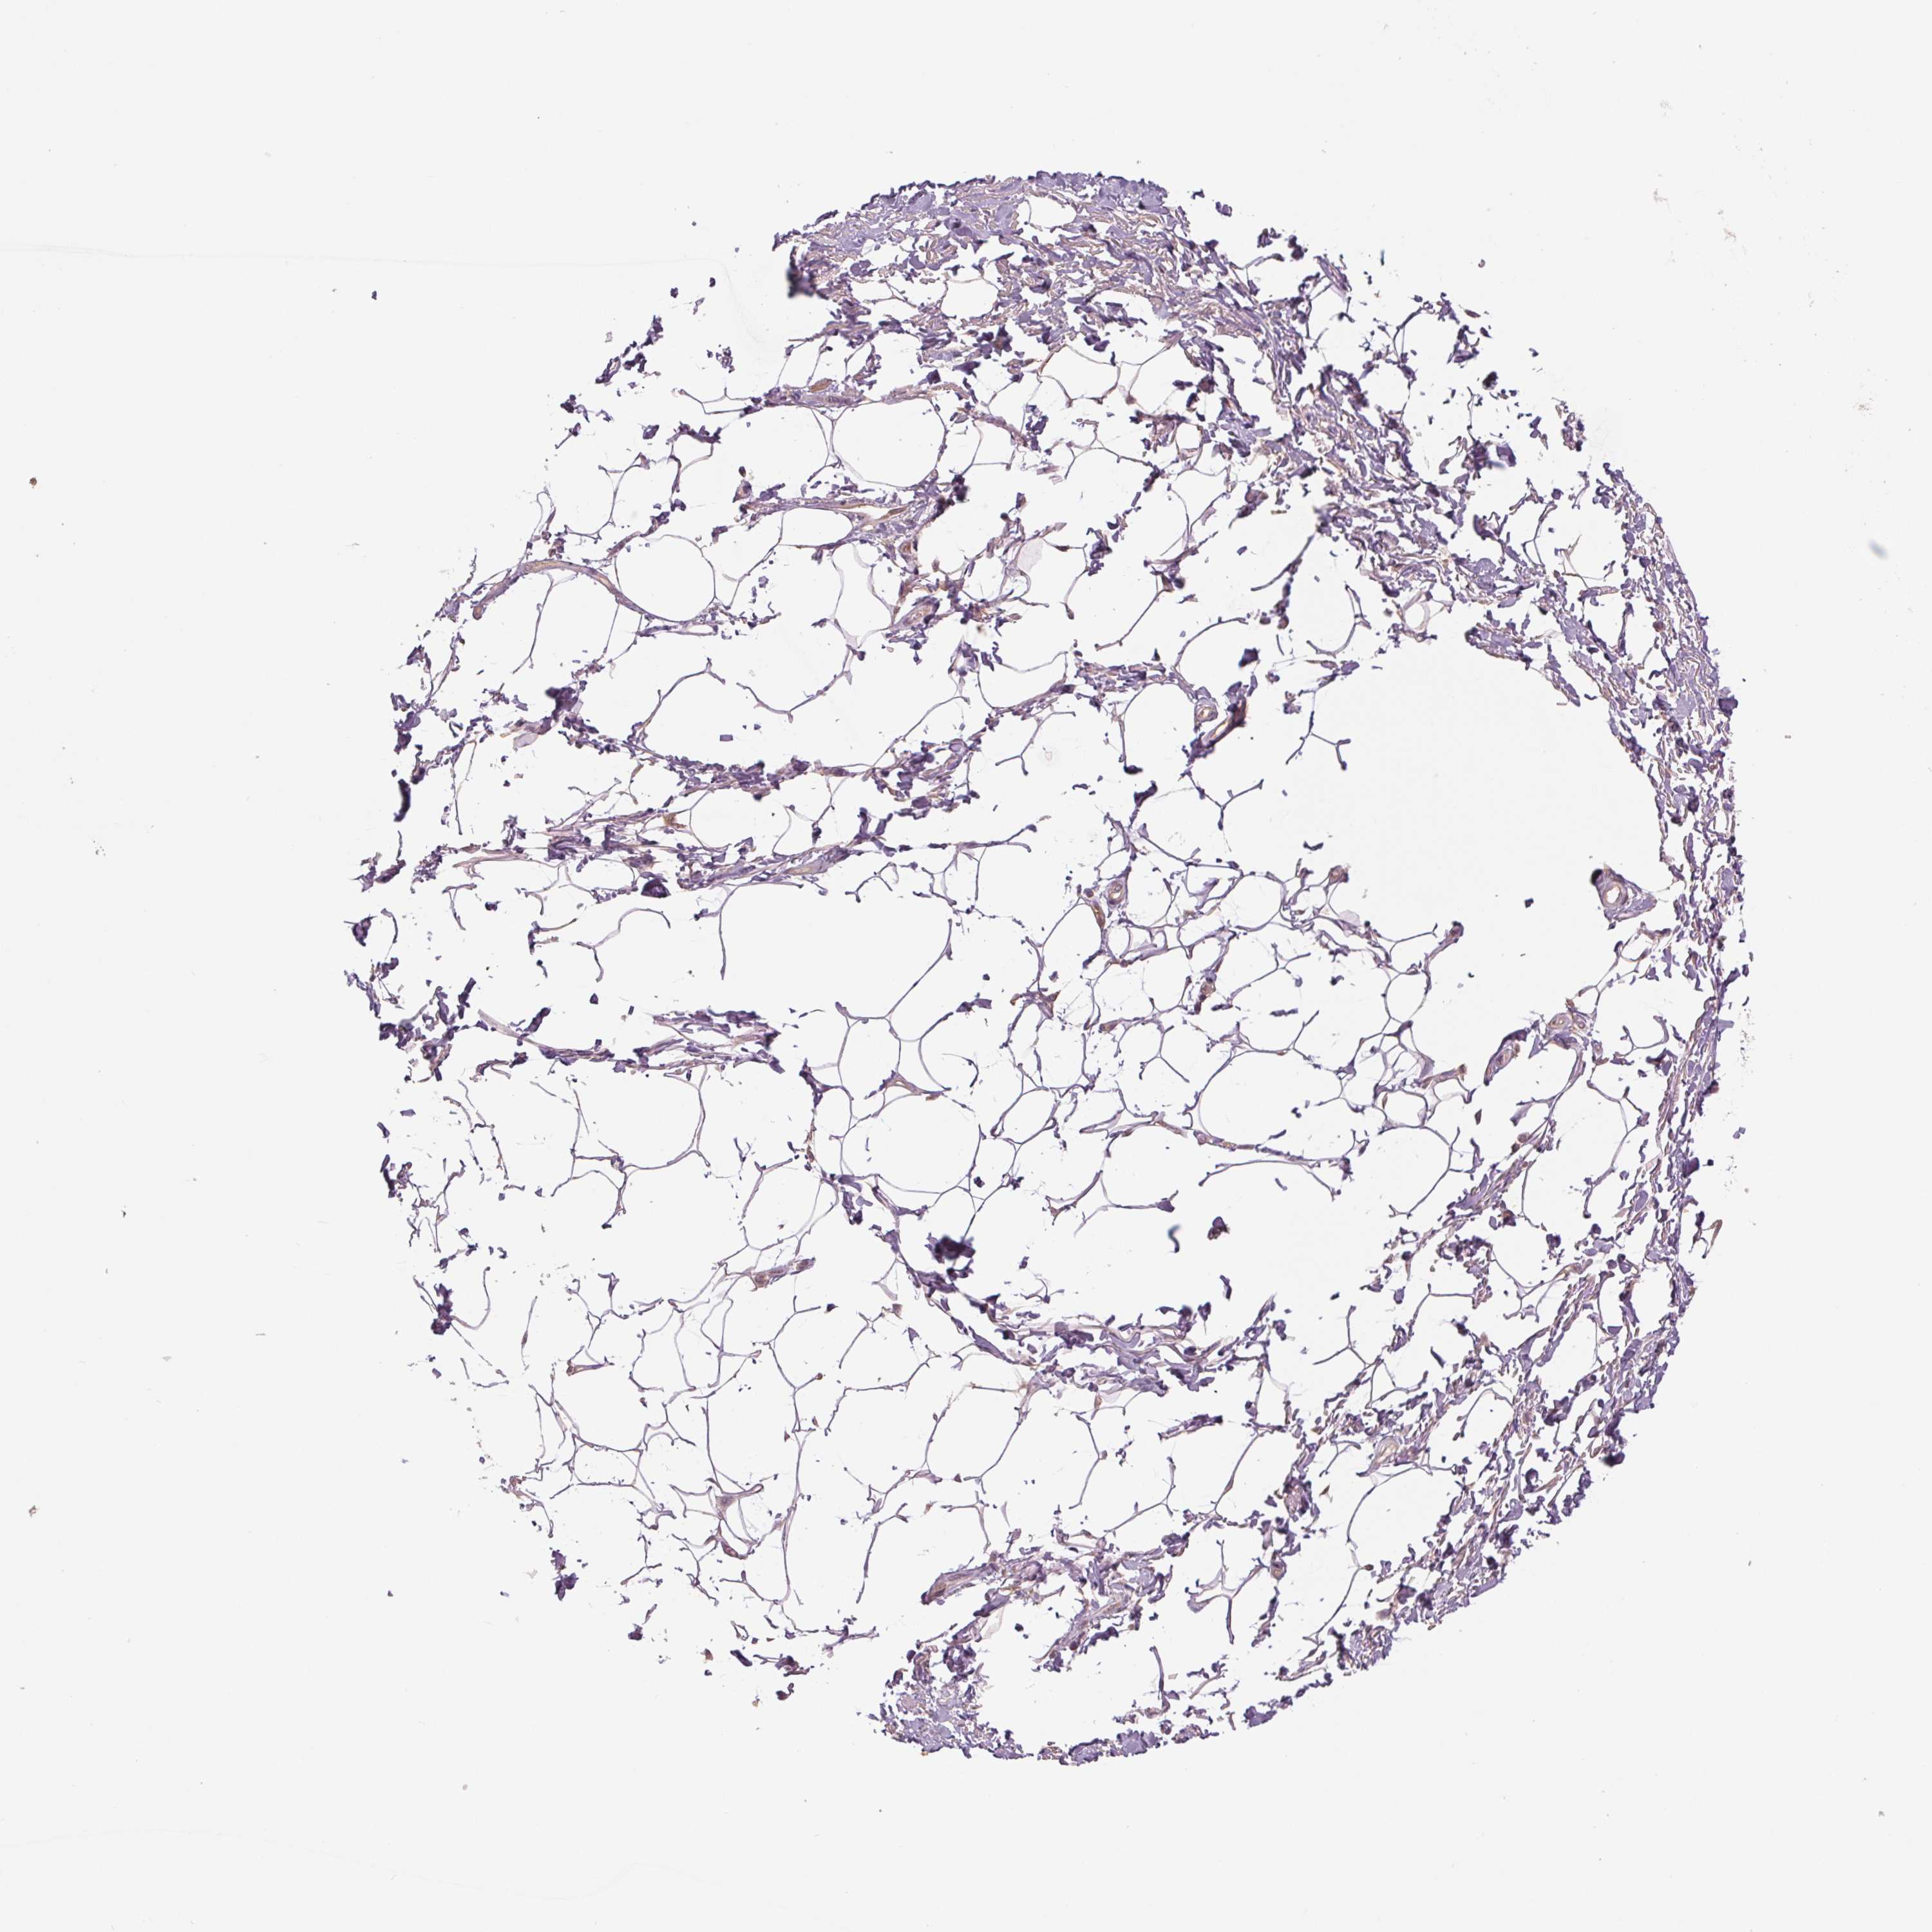

ADIPOSE TISSUE